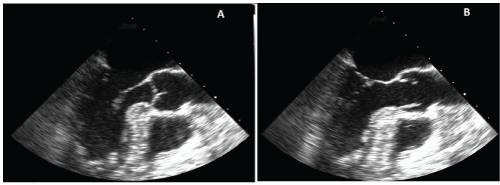

We report the case of a 60 year old right-handed female seen in neurologic consultation for recurrent stroke management. The patient presented with acute onset of binocular blurry vision, and an abnormal left peri-ocular sensation that started during casual conversation with a family member, and lasted about 2 hours. The event was associated with slurred speech and a persistent frontal headache. Upon arrival to our emergency department, visual and speech disturbances were resolved but a moderate headache remained. An initial neurological examination was unremarkable. A brain MRI reveals a subacute infarct in the left parietal lobe with petechial hemorrhages, old infarcts in the bilateral centrum semiovale, and chronic right occipital infarct (Figure1). The patient reported three prior admissions for acute stroke management. The first admission was for ataxia and visual changes, five months prior to the current presentation. Two months later, the patient was admitted for sudden-onset of non-fluent aphasia and right upper extremity weakness. Finally, she was admitted for right upper and lower extremity weakness, one month prior to the current presentation. Stroke work-ups performed during all three admissions did not reveal any specific causes for the stroke recurrences. She was left with multiple residual neurological symptoms after each event, including mild subjective gait abnormality which did not require assistive devices, intermittent episodes of stuttering speech, transitory visual symptoms (difficulties focusing on objects and reading because of "jumping" letters, and intermittent left-sided hemianopsia), and abnormal skin sensations around the left eye. In addition, the patient reported recurrent unilateral throbbing headaches of a mild intensity lasting hours, sometimes in association with visual and sensory symptoms. Despite recurrent strokes, the patient was prescribed Aspirin 162 mg daily.

Figure 1: Brain MRI without contrast at presentation

Subacute right parietal infarct with petechial hemorrhage is illustrated on

DWI (A), SWI (B) and FLAIR (C) images. Chronic right occipital (D-FLAIR

sequence), old bilateral corona radiata (E- FLAIR sequence) and right frontal

lobe (F- T2W sequence) infarcts are identified.